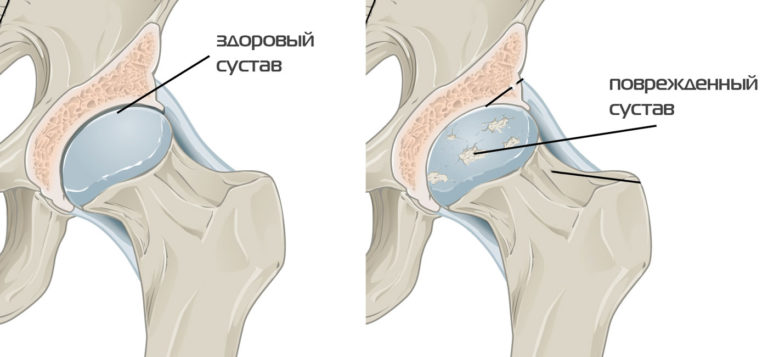

— коксартроз (остеоартроз тазобедренного сустава);

— асептический некроз головки бедренной кости;

— ревматоидный артрит с поражением тазобедренных суставов.

В основе всех этих заболеваний лежит поражение хряща с последующим вовлечением в патологический процесс костной ткани.